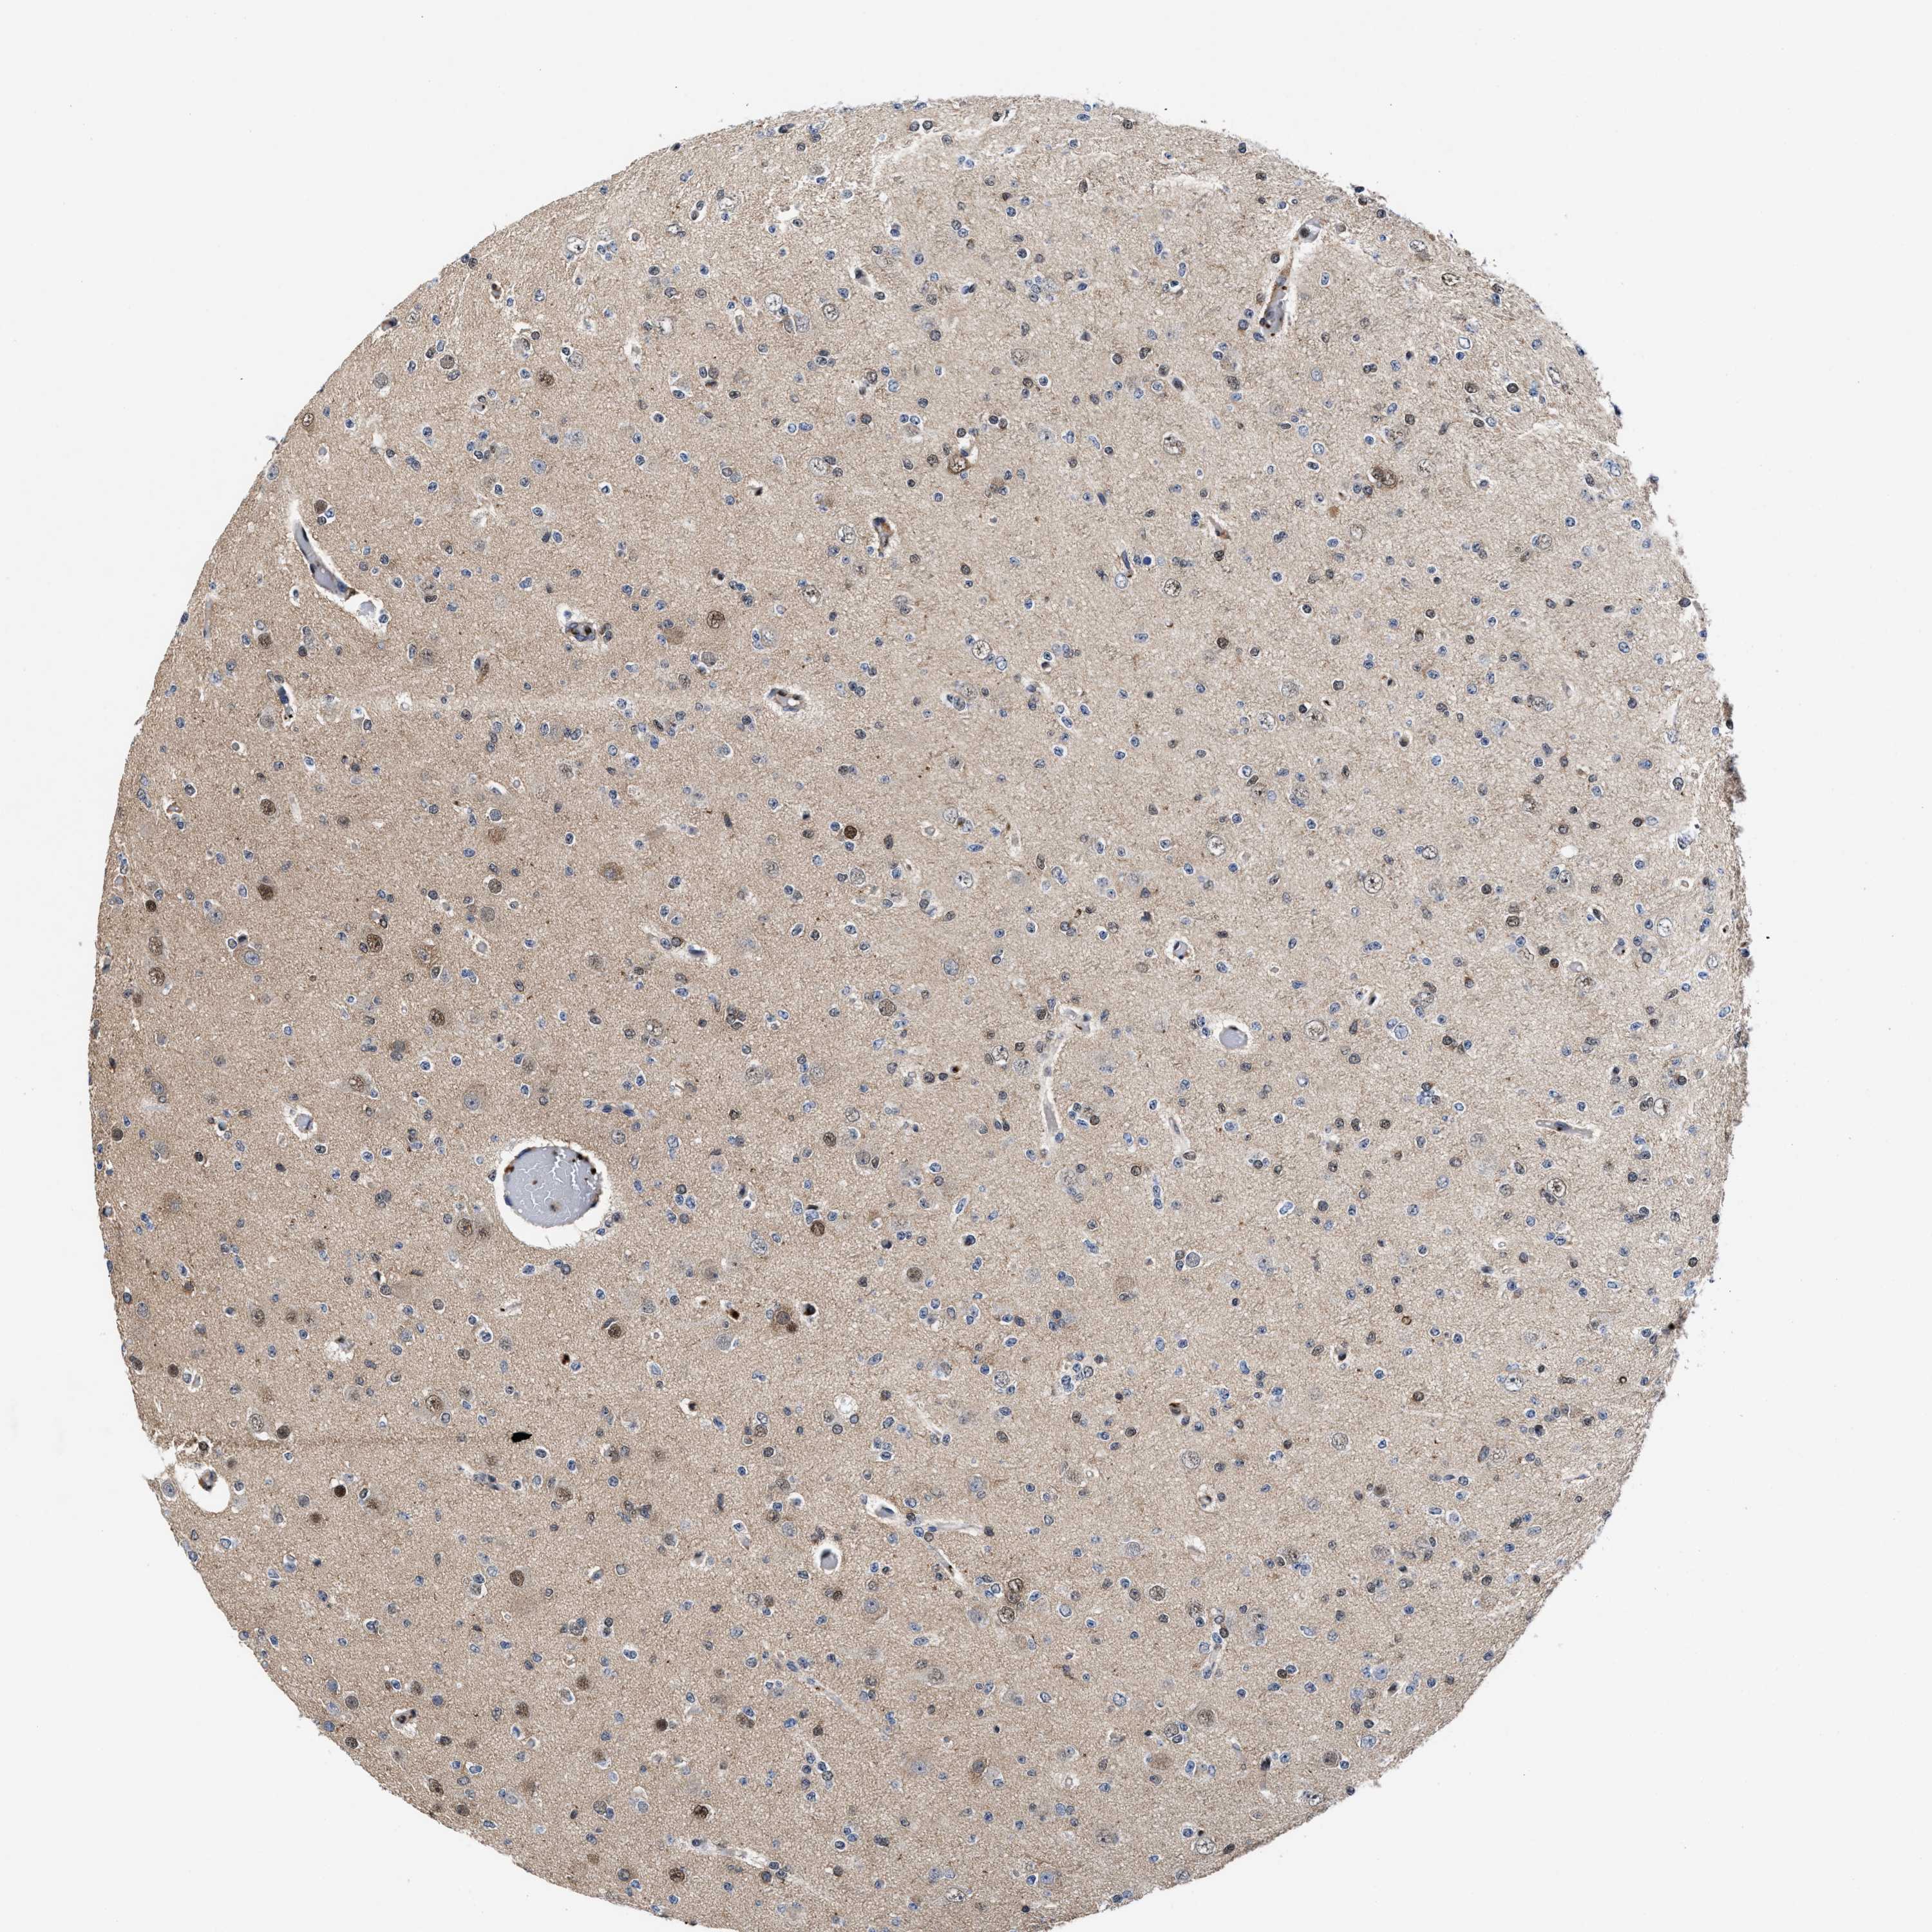

GLIOMA - Protein expressioni

A mouse-over function shows sample information and annotation data. Click on an image to view it in a full screen mode. Samples can be filtered based on level of antibody staining by selecting one or several of the following categories: high, medium, low and not detected. The assay and annotation is described here.

Note that samples used for immunohistochemistry by the Human Protein Atlas do not correspond to samples in the TCGA dataset.

Antibody stainingi

Antibody staining in the annotated cell types in the current human tissue is reported as not detected, low, medium, or high, based on conventional immunohistochemistry profiling in selected tissues. This score is based on the combination of the staining intensity and fraction of stained cells.

Each image is clickable and will lead to virtual microscopy that enables deeper exploration of all samples and also displays staining intensity scores, fraction scores and subcellular localization as well as patient and tissue information for each sample.

HPA022434

HPA022953

HPA022959

HPA028758

CAB007783

Glioma, malignant, High grade

Glioma, malignant, Low grade

Glioblastoma, NOS